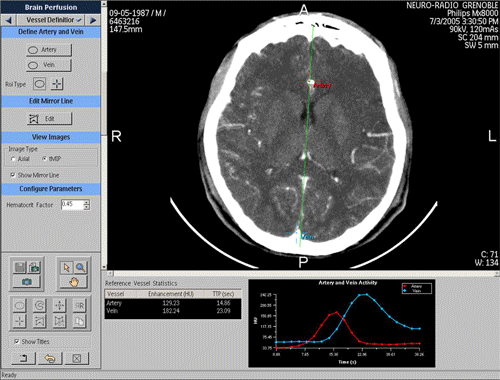

Comment je traite une TDM de perfusion cérébrale